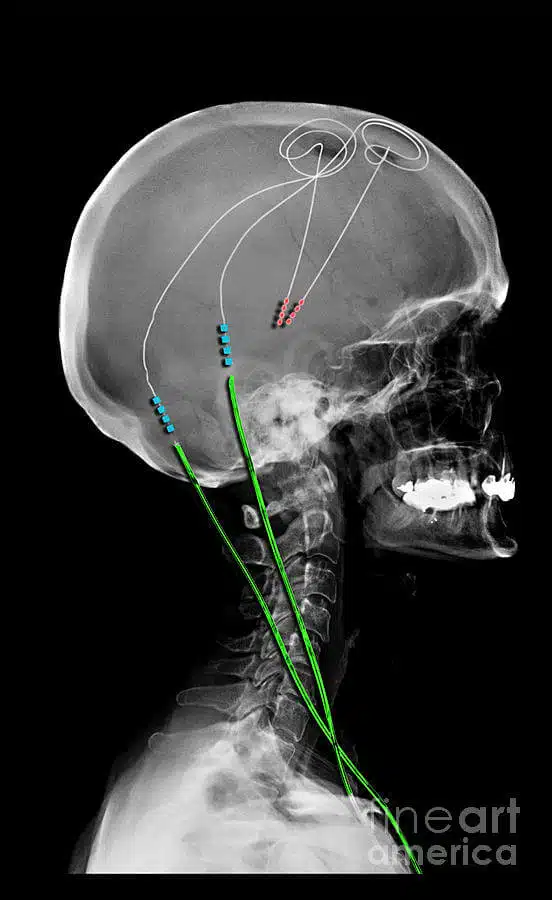

Deep brain stimulation (DBS) to treat Parkinson disease is a medical technique that includes placing electrodes or conductors in the brain, which send electrical impulses that change the unusual signals. This approach consists of four parts:

- Leads that end in electrodes that are implanted in the brain

- A small pacemaker-like device that makes the electrical pulses

- Delay leads that transmit electrical pulses from the pacemaker device

- Hand-held computer operator that adjusts the device’s signs